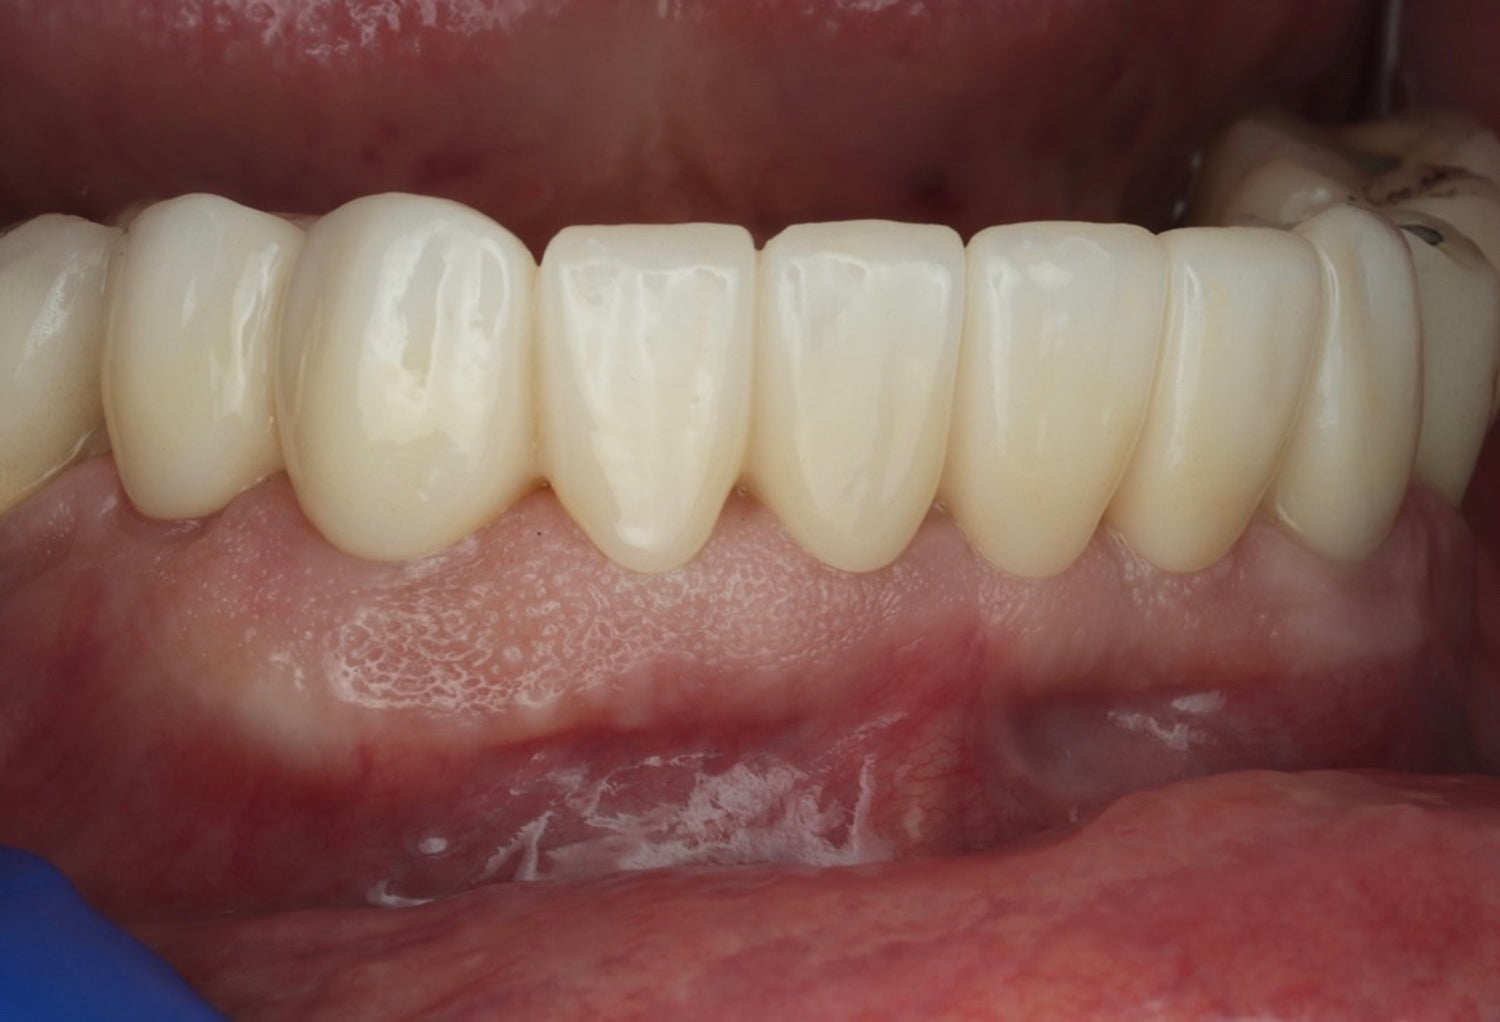

- Develop a thorough understanding of the critical soft tissue parameters that determine implant success

- Gain practical experience in soft tissue management and augmentation techniques for optimal peri-implant outcomes

- Explore the science behind Partial Extraction Therapy and understand its emergence as the gold standard in modern implantology

- Master Partial Extraction Therapy through systematic, step-by-step instruction and hands-on practice